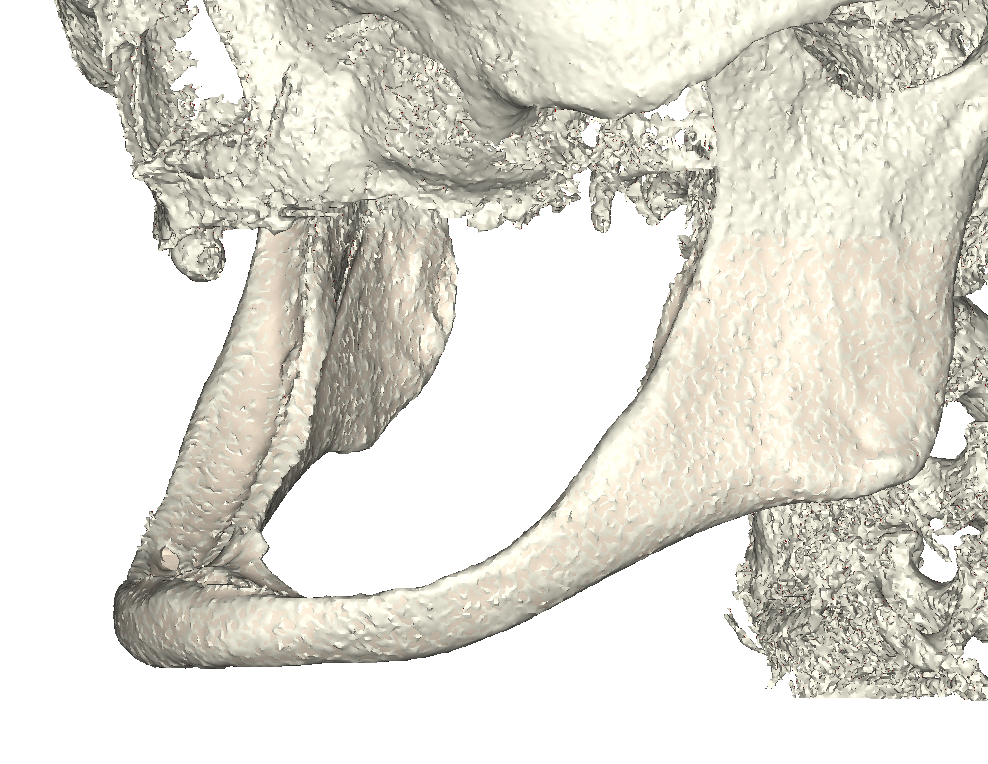

Paziente donna, di razza caucasica, di età 75 anni, edentula totale, che presentava una severa atrofia della mandibola con esposizione completa del nervo alveolare lungo tutto il corpo mandibolare fino al ginocchio dell’emergenza mentoniera (fig. 1a, b) e concomitante atrofia del mascellare di classe VI di C e H. La paziente non presentava patologie avverse al tipo di impianto iuxta scelto. Effettuata una ceratura diagnostica con prova denti mascellari e mandibolari per una corretta progettazione della dimensione verticale, si replicano i risultati mediante stampa 3D in resina con reperi radio-opachi per ottenere 2 dime occlusali da utilizzare durante l’acquisizione dei dati DICOM di una TC Spirale (layer thickness 0.6mm) al fine di costruire un modello osseo tridimensionale della Paziente in posizione ortognatica. Ciò al fine di progettare e produrre la struttura metallica dell’impianto iuxta osseo tripodale (per le ragioni anatomiche precedentemente esposte si è optato per questa soluzione), basandosi sulla posizione dei denti futuri riaccoppiando al dato radiologico dicom le scansioni delle dime stesse (fig. 2).

atrofia della mandibola e nervo scoperto

Fig. 1(a). Vista coronale atrofia mandibola ed esposizione nervo.

Modello 3D

Fig. 1(b). Modello 3D.